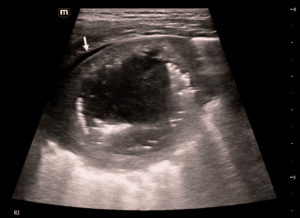

Case 1: Pilonidal abscess

A 23-year-old female presented with a history of acute pain at the natal cleft area. POCUS revealed a small pilonidal cyst with no craniocaudal extension. The patient underwent localized excision (Figure 1).

Figure 1. Infected pilonidal cyst. A) Natal cleft with small opening. B) Using high frequency linear probe with a layer of gel to scan the natal cleft area. C) Ultrasonographic sagittal view showing the pilonidal cyst and hair within (arrow) and the single pit (arrow head). No craniocaudal extension. D) Post excision.